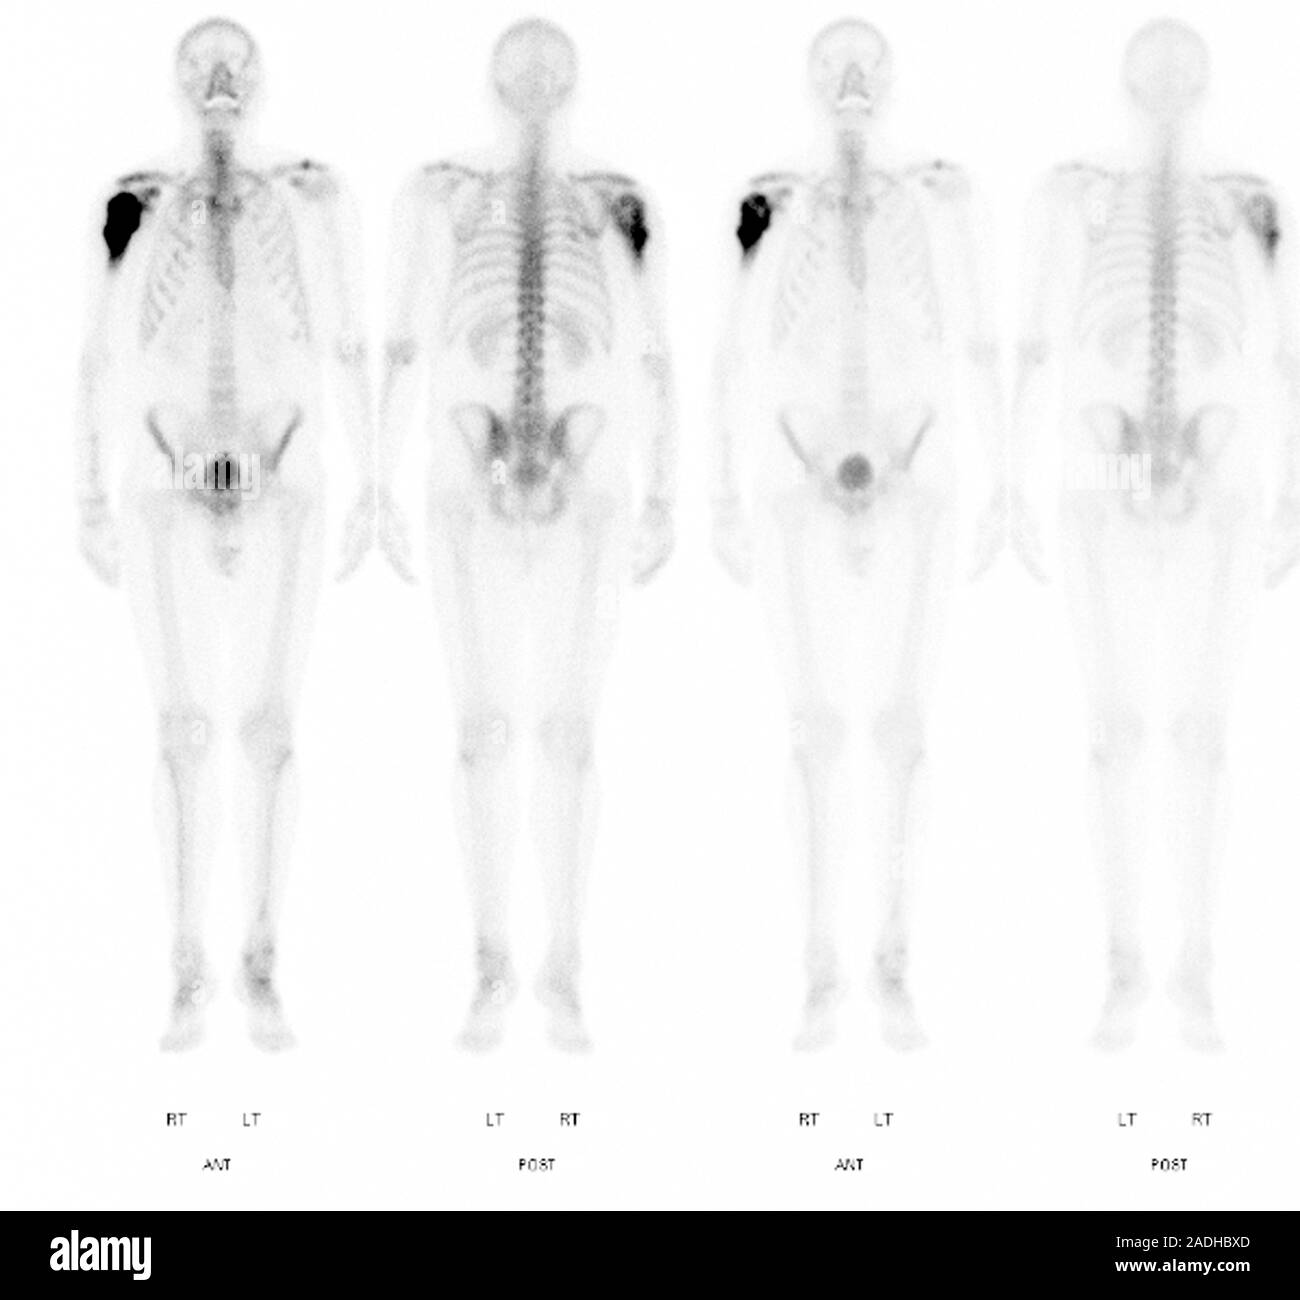

From www.alamy.com

Bone cancer. Scintigrams (gamma scans) of a 51 year old man with a Chondrosarcoma Bone Scan Chondrosarcoma is a rare cancer that most often forms in the bone, but can also very rarely appear in the soft tissue. It is the most common bone cancer found in adults. Tests and procedures used to diagnose chondrosarcoma include: Chondrosarcoma is a rare type of bone cancer that develops in cartilage cells. Your doctor may ask about your signs.. Chondrosarcoma Bone Scan.